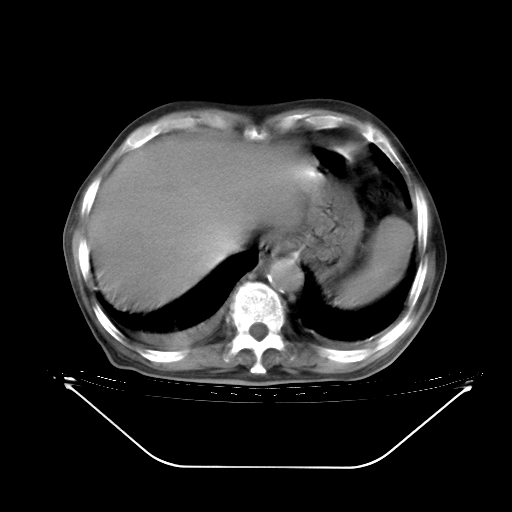

胸腹部CT,诊断意见:左上肺叶钙化灶、左侧胸膜局限性增厚并钙化、胆囊炎。描述部分肺组织呈磨玻璃样改变。

今天复查肺部CT,发现双肺广泛磨玻璃样改变。所以我把3月19日和5月9日相隔50天的肺部CT上传。请大家会诊。

2009年3月19日肺部CT片。

5月9日肺部CT(在4月27日齐鲁医院肺部CT描述部分肺组织磨玻璃样改变,12天后肺组织广泛磨玻璃样改变)